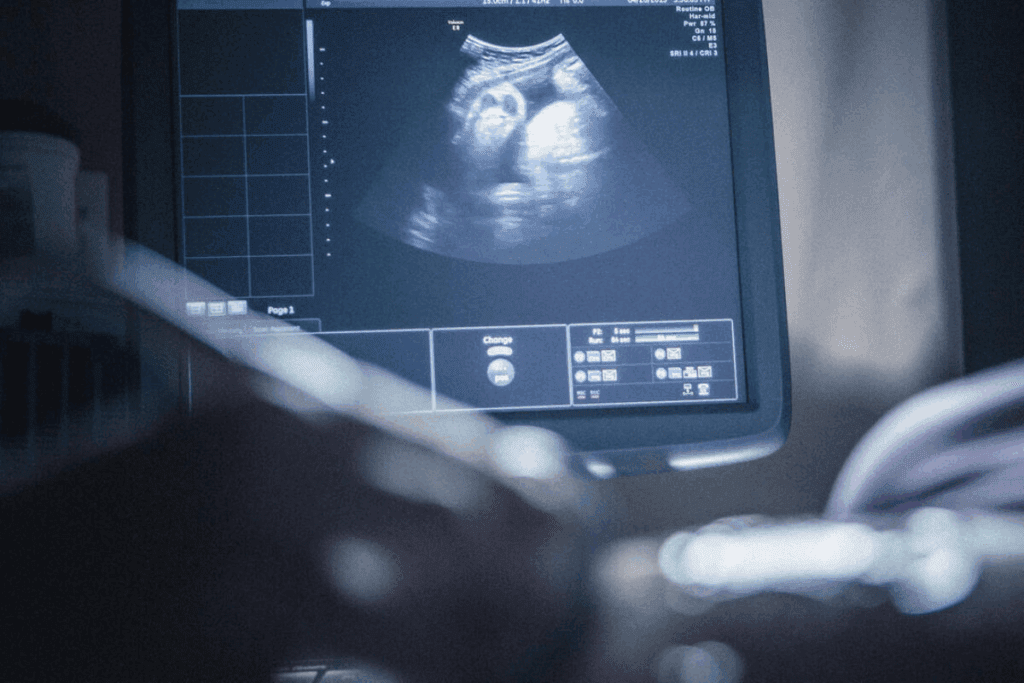

At 8 weeks pregnant, you’re at a big milestone. An ultrasound at this time is both thrilling and a bit scary. Your baby is as small as a raspberry, about 1.6 cm long.Guide on the fetal structures visible in an 8 week sonogram what to expect from the procedure. Prepare for your 8 week sonogram what to expect.

This scan shows important parts like the gestational sac, yolk sac, amniotic sac, and the embryo. Seeing the fetal heartbeat is a good sign, showing your baby is doing well.

The 8-week ultrasound shows important structures for the baby’s growth and the pregnancy’s health. It gives parents a peek into their baby’s development during this key time.

Gestational Sac Measurements and Appearance

The gestational sac is seen first on an ultrasound. It’s where the embryo starts and shows if the pregnancy is healthy. Doctors use its size to check how the pregnancy is going and guess the baby’s age.

Yolk Sac Function and Significance

The yolk sac is key for the baby’s early nutrition before the placenta is ready. Seeing it on the ultrasound tells doctors about the baby’s health. It shows how well the baby is getting the nutrients it needs.

Amniotic Sac Development

The amniotic sac wraps the embryo in a safe, fluid-filled space. It protects the baby from outside pressures and keeps the environment stable. Seeing the amniotic sac on the ultrasound is a good sign for the baby’s growth.

Early Placental Formation

At 8 weeks, an ultrasound shows how much your baby has grown. Your baby is now about 1.6 cm long and looks like a raspberry.

Size and Appearance of Your Baby

Your baby’s size and look tell a lot about their growth. The embryo is about 1.6 cm long and their features are getting clearer. Their curled shape and early limbs give them a raspberry-like look.